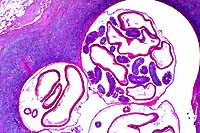

10x

obj.

- Case 23-3. Liver. A granuloma composed of necrotic

debris surrounded by waxy eosinophilic material (amyloid) and

degenerate inflammatory cells replaces hepatic parenchyma.

Congo

red, 20x obj.

- Case 23-3. Liver. Hepatic plates are separated by

amorphous deposits of red staining material (amyloid) and low

numbers of lymphocytes.